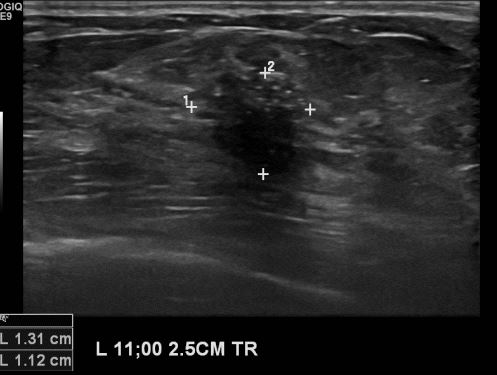

상기환자 건강검진상 이상 소견으로 내원하신 60대 여성분으로 본원 초음파상 좌측

11시 방향에 의심스러운 멍울 조직검사 시행하여 좌측 유관암 진단 되었습니다.